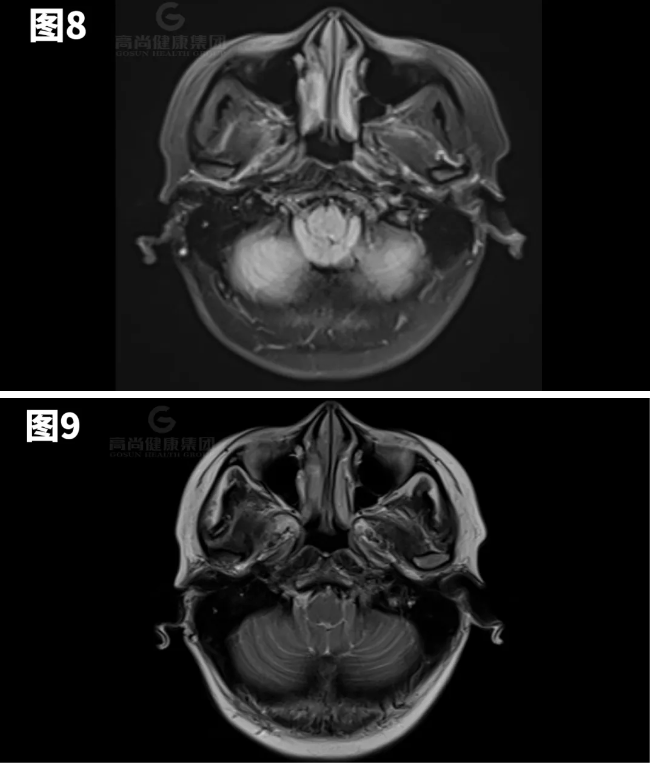

图8-11示小脑扁桃体向下疝出约7mm。

矢状位:扁桃体延伸到枕骨大孔下方,脑干压迫斜坡。

横断位:移位的扁桃体导致周围脑脊液闭塞、髓质前移以及脊髓动脉和椎动脉受压。